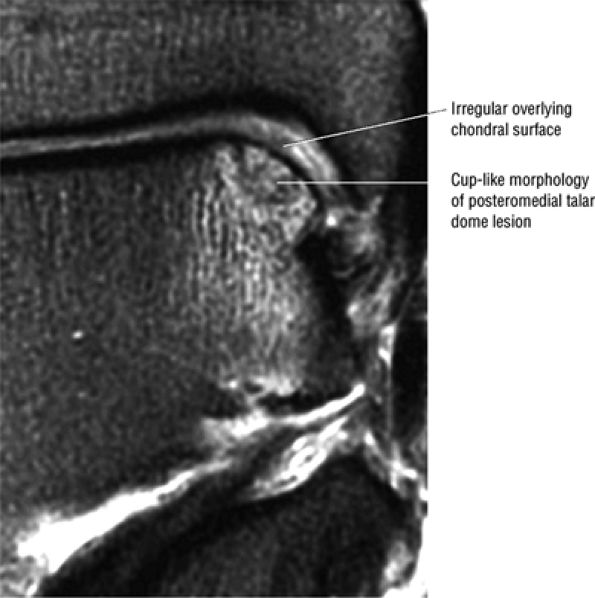

FIGURE 5.92 ● Anterolateral and posteromedial locations of osteochondral lesions of the talus. The lateral lesions tend to be shallower and wafer-shaped, whereas the medial lesions are deeper and cup-shaped.

FIGURE 5.93 ● Medial cup-shaped osteochondral lesion (OLT). Medial OLTs are more common than lateral ones, but lateral lesions are associated with trauma in over 90% of cases. Medial lesions are ascribed to trauma in about 70% of cases. Coronal FS PD FSE image.